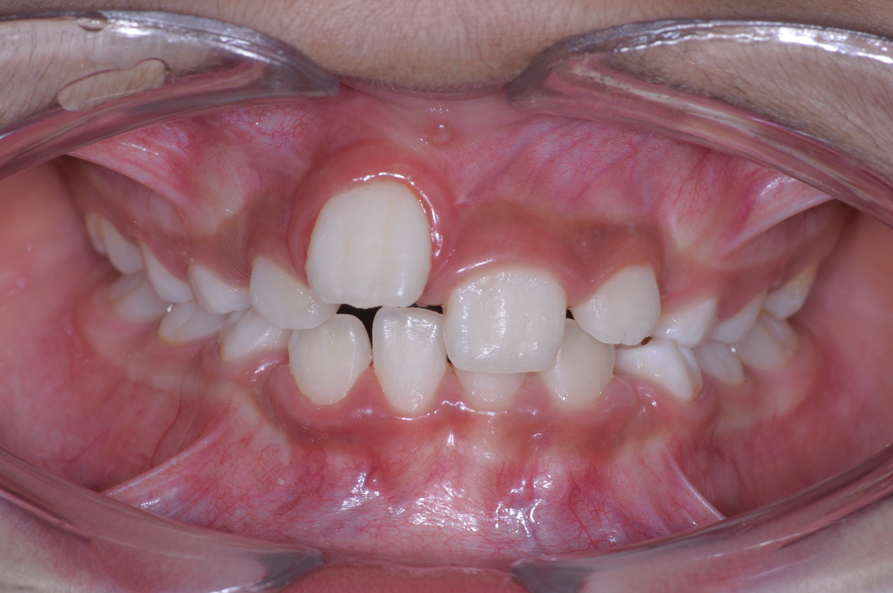

The following case illustrates the complete surgical/orthodontic treatment sequence for an impacted maxillary right central incisor. An 8½-year-old patient presented with a chief complaint of crowded teeth. The maxillary left central incisor was the only erupted incisor at the time of consultation (Figure 2 and Figure 3). Crowding was clinically diagnosed visually by the prominence of the unerupted right central incisor in the vestibule, and this was confirmed with a panoramic radiograph (Figure 4).

Fig 2. Initial situation of case involving an impacted maxillary right central incisor, frontal view (Fig 2) and occlusal view (Fig 3).

Figure 2

Fig 3. Initial situation of case involving an impacted maxillary right central incisor, frontal view (Fig 2) and occlusal view (Fig 3).

Figure 3